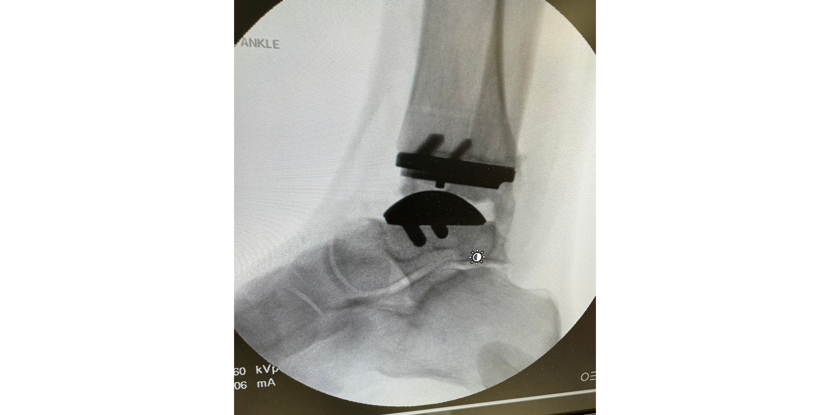

- Additional Specialties: Foot Surgery (Board Certified), Reconstructive Rearfoot/Ankle Surgery (Board Certified), Total Ankle Replacement

- Ankle replacements

- Ankle replacement

Ankle Replacement: Is It Right For You?